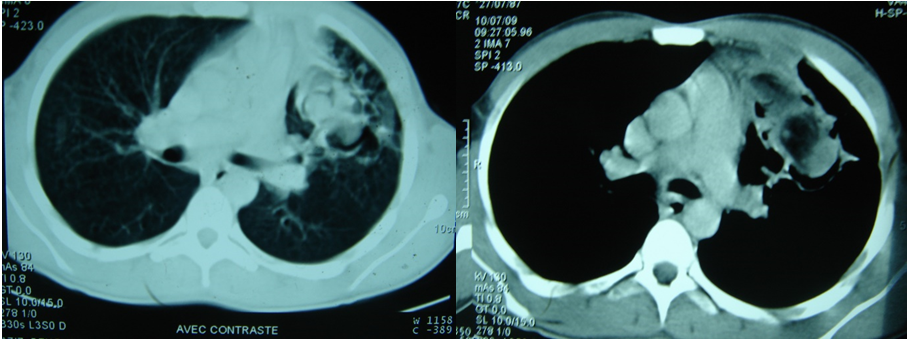

A 22-years-old nonsmoker male treated of pulmonary tuberculosis in 2007 presented with a one-year history of intermittent episodes of cough and hemoptysis, thoracic left pain, dyspnea induced by high activity, weight loss, fever, and night sweats. A computed tomography (CT) chest scan showed a heterogeneous tumor with cavitary lesion, occupying the left upper lobe. It appeared to be adherent to the aortic arch and the level of the main pulmonary trunk (figure 1). Bronchoscopy revealed a very important inflammation of the left bronchial tree (3rd degree), with bleeding at least contact, and the muco-purulent secretions whose bacteriological and mycotic examination is unremarkable. Bronchial biopsy revealed a nonspecific chronic inflammation. Pulmonary function test results showed mild obstructive ventilatory disorder limited to small aerial ducts; with a forced expiratory volume in one second of 82%. The aspergillum serology was negative. Routine laboratory testing was entirely normal including testing for koch bacillus in sputum. The diagnosis of pulmonary aspergilloma in its complex form was suspected, the patient initially prepared with an antibiotic and hemostatic treatment before the surgery. A left posterior-lateral thoracotomy was realized, the exploration discovers a bulky hard yellowish tumoral mass of approximately 7 cm, was identified in the culmen. There was connection to mediastinal fat, and lingula was completely hepatized. the lung was completely adherent to see a total symphysis especially at the level of the apex making the adhesiolysis and the dissection of the hilum very difficult and bleeding. We opted for a left upper lobectomy carrying in the monobloc mediastinal mass. The analysis of the operative piece shows a cystic tumoral process with thick wall, pilous and friable contents. The patient presented favorable evolution and was discharged on postoperative day 5. The final histological study concluded that it was a primary intrapulmonary mature teratoma with complete resection of the tumor. Follow up during the next years showed no sign of recurrence.